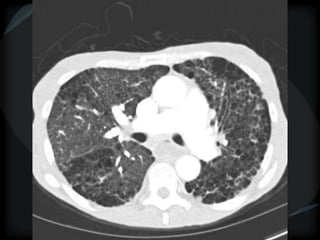

Airspace Patterns

 Diffuse ground-glass

 Patchy consolidation (peripheral)

 Inter and intralobular septal thickening / ground glass/crazy paving

 Reverse halo/atoll sign

 Hogshead cheese sign

 Perilobular pattern

 Organising pneumonia – COP/BOOP

 Chronic eosinophilic pneumonia

 Alveolar proteinosis

 Desquamative interstitial pneumonitis

 Alveolar microlithiasis

 Alveolar sarcoid

 BAC